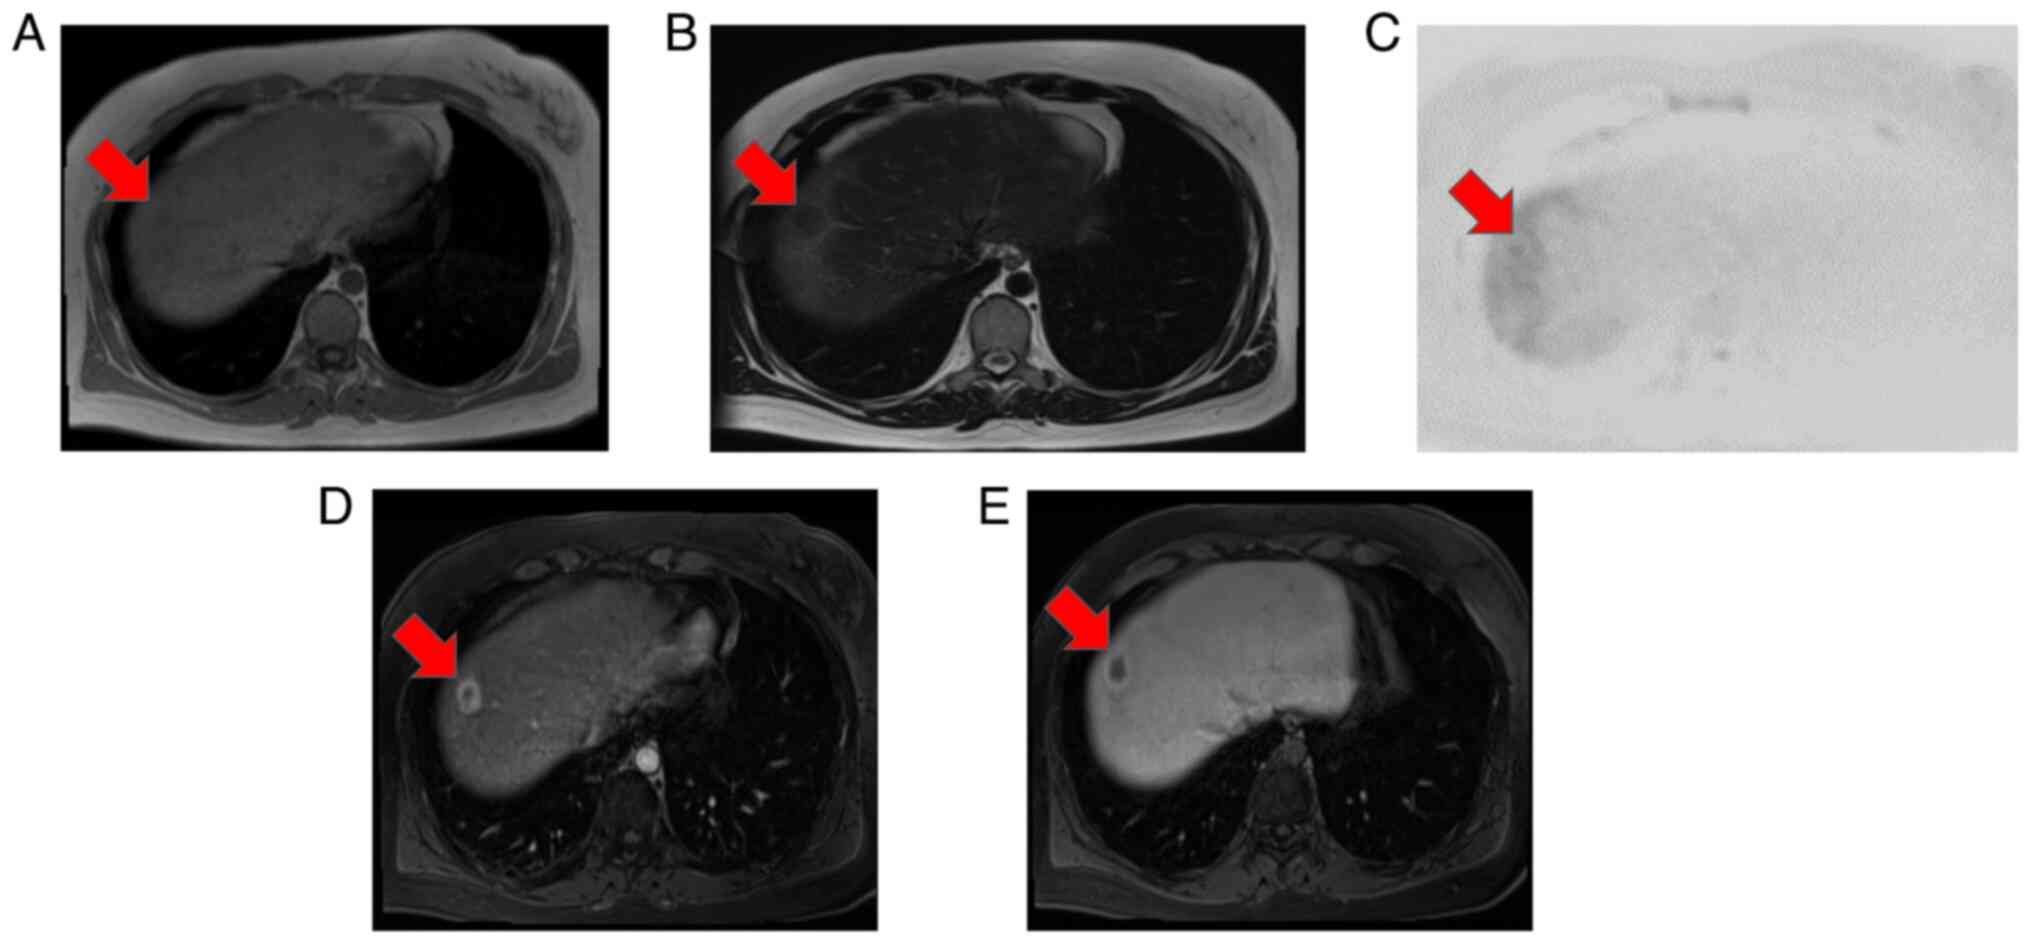

Ultrasonography revealed multiple hyperechoic tumors in the liver (Fig. 1A-C). Magnetic resonance imaging (MRI) was performed before a dynamic computed tomography (CT) scan to limit radiation exposure (8,12). MRI examinations were performed using 1.5-T MR systems (MAGNETOM Sola, Siemens Medical Solutions, Erlangen, Germany). The gradient strengths were 45mT/m with a slew rate of 200T/m/second. Eighteen-element phased array matrix coil was used for signal reception. MRI showed that the main tumor in segment (S)8 had low signal intensity on both T1- and T2-weighted images and slightly high signal intensity on diffusion-weighted imaging (Fig. 2A-C). Contrast-enhanced MRI revealed that the S8 tumor was enhanced in a ring shape during the early contrast phase (Fig. 2D). In the hepatobiliary phase, the periphery had a high signal intensity and the interior had a low signal intensity (Fig. 2E). Near the main tumor in S8, two small tumors were heavily contrasted in the early phase but were not identified in the hepatobiliary phase (Fig. 3). Numerous tumors suspected to be lipomas, focal nodular hyperplasia or arterio-portal shunts were also observed in the liver.

Figure 1

Ultrasonography showed multiple hyperechoic tumors in the liver. (A) 30 and (B) 18-mm hyperechoic lesion was detected near the gallbladder (arrow). (C) Multiple hyperechoic lesions were detected in the right lobe of the liver (arrows).